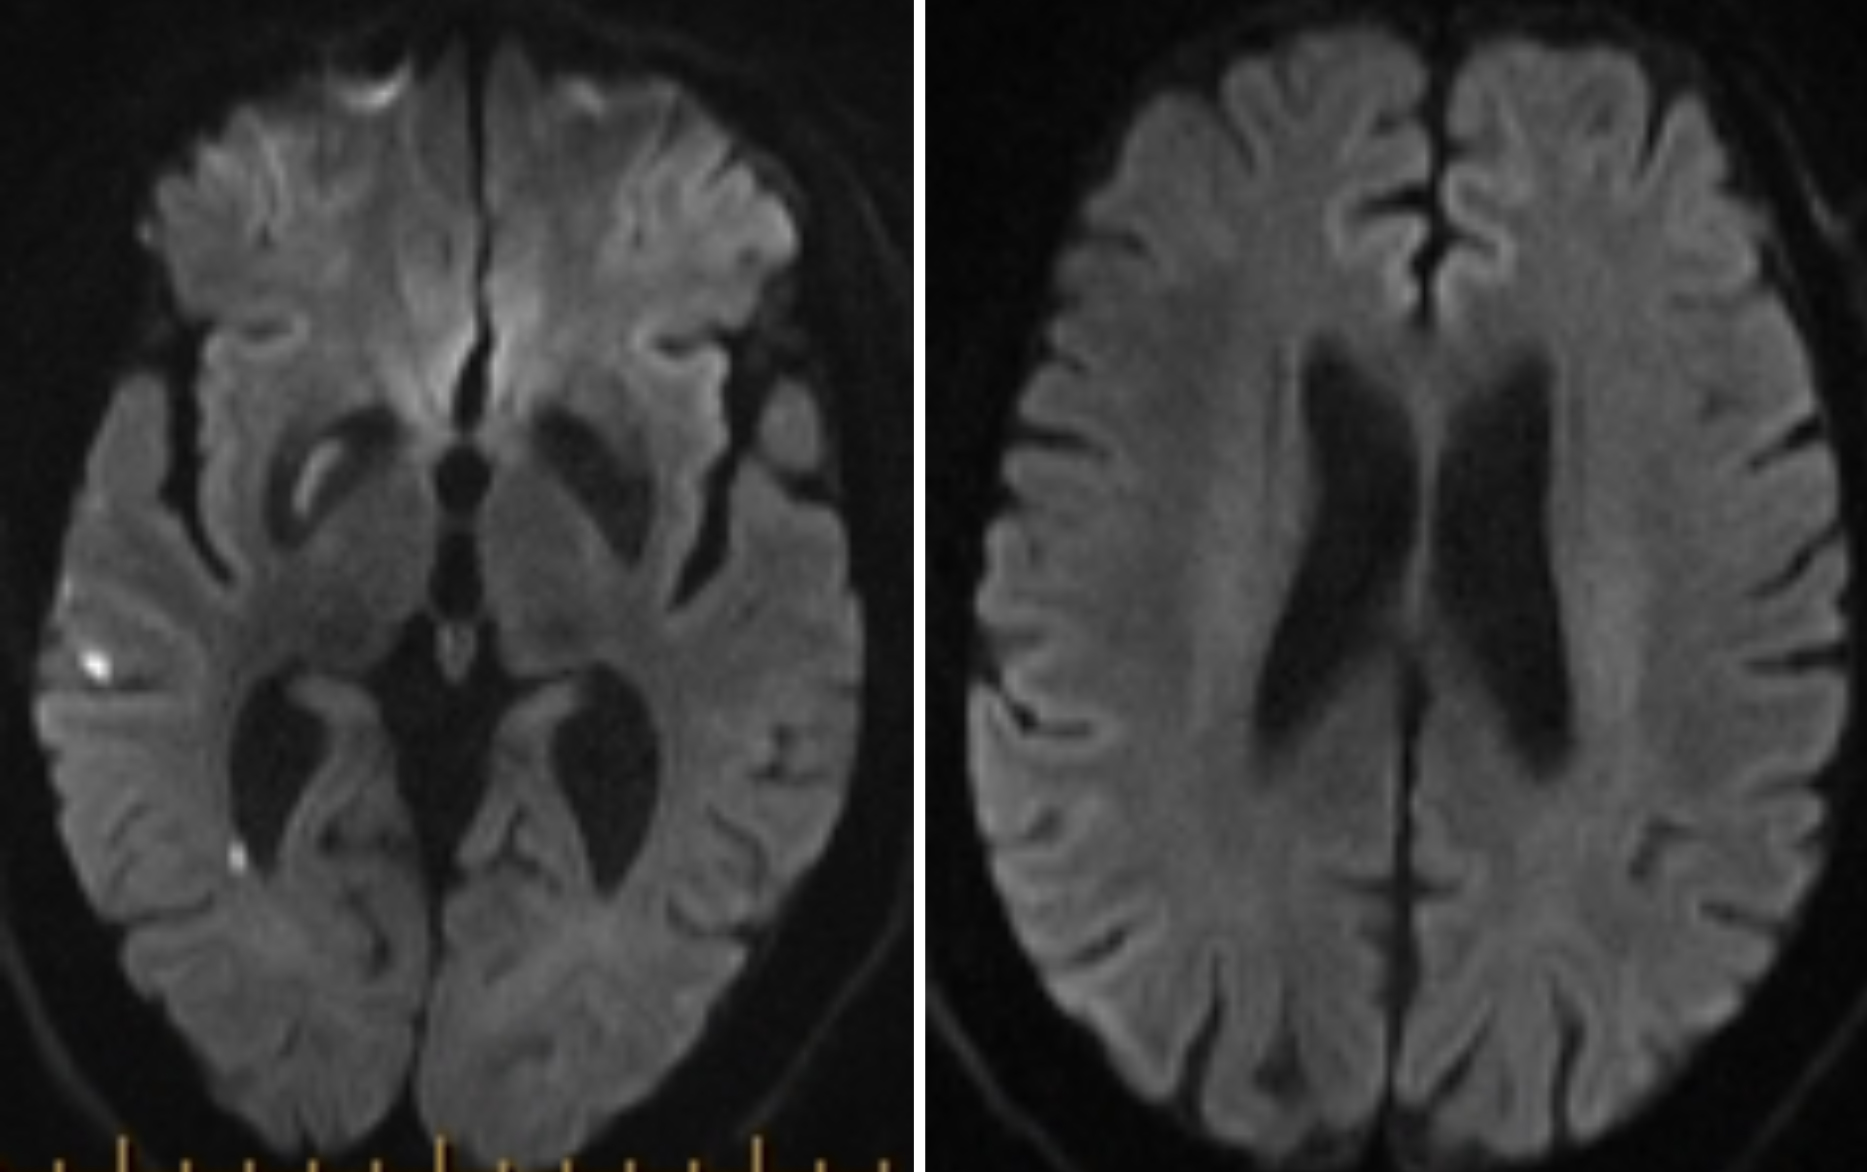

The patient was sent DTA and a Sine Spin head CT was done (Figure 3). Thrombolysis in cerebral infarction (TICI) 3 was achieved after 1 pass (Figure 4). Time from door to recanalization was 43 minutes. Figure 5 shows the patient’s MRI after 24 hours.